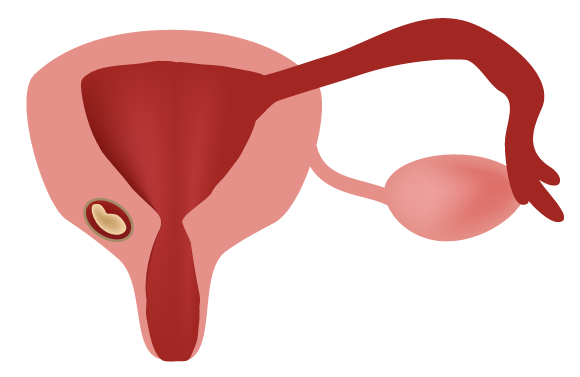

مصدر مصطلح الحمل الاكتوبيّ، الحمل خارج الرحم أو الحمل المنتبَذ (Ectopic pregnancy)، هو الكلمة اليونانيّة "إكتوبوس" (Ektopos)، التي تعني "خارج المكان". تتجذّر البويْضة المخصّبة في هذا الحمل خارج الرحم بدلًا من داخله. غالبًا – في حوالي 97 بالمائة من الحالات – ما يتجذّر الجنين في حالة الحمل المنتبذ في البوق الرحميّ (قناة فالوب). قد يحصل التجذّر، في حالات نادرة نسبيًّا، في المبايض، أو في عنق الرحم أو في تجويف البطن.

يشكّل الحمل المنتبذ خطرًا على حياة المرأة، وهو العامل الأكثر شيوعًا لوفاة النساء الحوامل خلال الثلث الأول من الحمل – تبلغ فيه نسبة الخطر على الحياة 9 إلى 14 بالمائة من الحالات. تبلغ نسبة شيوع حالات الحمل خارج الرحم اثنين بالمائة، أي يحصل التجذّر خارج الرحم في اثنتين من كلّ خمسين حالة إخصاب. نسبة شيوع هذه الظاهرة في هذه الأيام هي أكثر ممّا كانت عليه في الماضي، وهي في ازدياد في العقود الأخيرة بسبب عوامل الخطورة، منها التدخين، علاج الخصوبة، ممارسة الجنس في جيل مبكّر، الحمل في جيل متقدّم، استخدام اللولب الرحميّ لمنع الحمل، عمليّات جراحيّة في الحوض و حمل منتبذ سابق.

كيف يمكن الكشف عن الحمل خارج الرحم؟ من الصعب اكتشافه خلال الأسابيع الأولى من الحمل لأنّ الشكاوى التي من شأنها أن تثير الشكوك لا تظهر إلّا مع التقدّم في الحمل، غالبًا من ستة إلى ثمانية أسابيع، وهي تشمل آلامًا في أماكن متفرّقة من البطن، نزيفًا دمويًّا مهبليًّا، غثيانًا، دوخة، وقد تصل إلى فقدان كمّيّة كبيرة من الدم وفقدان الوعي. أخطر المضاعفات التي تسبّب النزيف وتهدّد الحياة هي تمزّق قناة فالوب (البوق الرحميّ). البوق الرحميّ ليس مهيّئًا – كما الرحم الذي يمكن أن يتمدّد ويزداد حجمه كي يحتوي الجنين الآخذ بالنموّ- لاحتواء كيس الحمل، ولا يصمد بالضغط الذي يؤثّر به الجنين عليه من الداخل، الأمر الذي قد يؤدّي إلى تمزّقه وحدوث نزيف دمويّ.